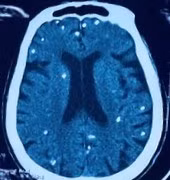

Ở người, ngoài vị trí cơ, nang sán có thể được hình thành tại các vị trí nguy hiểm như não, mắt, có thể gây ra động kinh, rối loạn tâm thần...